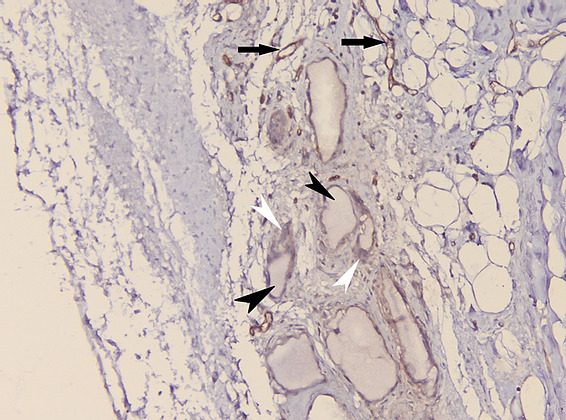

The histolopathological analysis performed shows in the meshes of the prosthetic material, fibrovascular tissue and minimal polymorphic inflammatory infiltrate (lymphocytes, plasma cells and polymorphonuclear neutrophils) and moderately frequent multinucleated giant cells of the “foreign body” type at the interface with the hydroxyapatite as well as osteoclasts at the interface with the hydroxyapatite nanocomposite material. At different levels in the muscle tissue and in the corresponding sclera, amorphous, acellular material (mono and multifilament surgical threads) bordered by multinucleated giant cells of the “foreign body” type is observed. (Figure 11,12). It can be observed that the invasion of the implant with fibrovascular material begins from the incision and the initial suture area, and the presence of multinucleated giant cells of the foreign body type in not very large numbers attests to good compatibility, at least equal to that of the suture material.

Figure 14: Microscopic appearance of the hydroxyapatite implant in CD34 immunohistochemical staining. The muscle tissue is negative for CD34 (black arrow), the presence of vascular endothelium as a positive internal control (white arrowhead) and fibroblasts, positive for CD34, at the level of the prosthetic material – hydroxyapatite (white arrow);

Discussions CT analysis performed one month postoperatively shows nanostructured hydroxyapatite density values in the scleral sac lower than the bone density of the animal model, but progressively increases at 2 months postoperatively. In terms of density, this is above the density of fibrous tissue but below the bone density of the animal model. In a study published by Froum et al., where a sinus allograft was implanted in humans and allowed to heal, it was demonstrated that a bone volume of about 25% of normal bone volume is sufficient to support a titanium implant8. In the study we found a progressive increase as healing progresses with a maturation of the newly formed tissue from type 2 bone density (300-500 HU) to type 1 bone density (over 500 HU). Histopathological analysis shows bone tissue formation inside the implant, the presence of fibrovascular tissue but also inflammatory cells. Also, the large number of osteoclasts is a marker of the degradation of nanostructured hydroxyapatite in the local production of new bone. Considering the existence of an extensive infectious process in one of the subjects that required the administration of general and local antibiotics for a longer period, the presence of inflammatory tissue rich in polymorphonuclear cells and lymphocytes is a valuable marker of the existence of this complication. However, it is known that inflammatory tissue transforms over time, after the resolution of the infection, into fibrous, scar tissue, which for this type of implant does not constitute a disadvantage, it can only be considered the possibility that the fibrosis process inside the implant may last longer. Conclusions: The progressive increase in the formation of fibrous tissue and new bone as healing progresses with a maturation of the newly formed tissue from type 2 bone tissue (300-500 HU) to type 1 bone tissue (over 500 HU) argues for the possibility of adapting a rapid dowel and screw to the animal model. In addition, histological analysis of the newly formed tissue inside the scleral sac reveals the rapid formation of bone and osteoid material alongside fibrovascular tissue, which is an important premise in promoting nanostructured hydroxyapatite materials in the prosthesis of the anophthalmic cavity. Moreover, the presence of CD31 and CD34 positive cells argues for rapid angiogenesis and fibrogenesis.